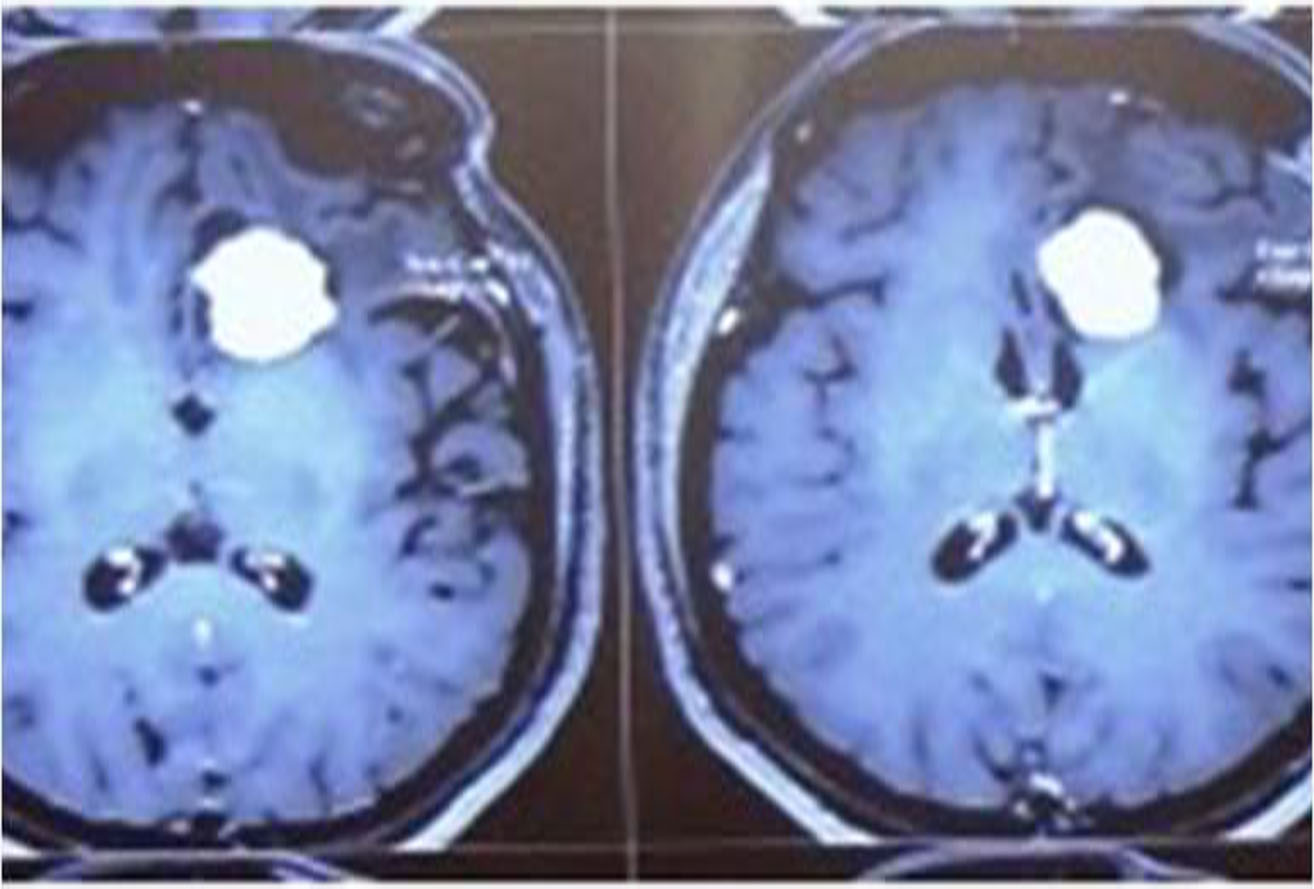

Brain injuries can be minor or major life threatening. The signs and symptoms depend on the severity of injury.

Minor injuries are usually treated with medications and constant monitoring. Moderate to severe injuries require treatment in neurosurgical ICU and may require emergency surgery.